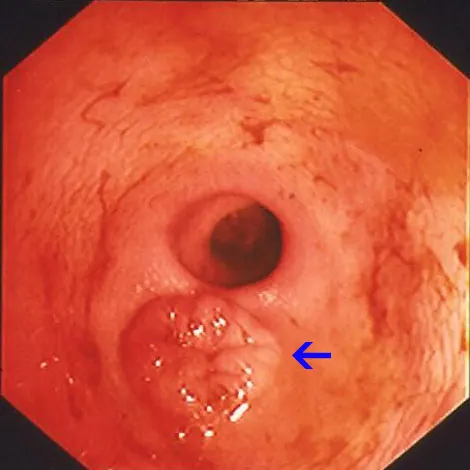

Retrograde ileoscopy should be performed as part of routine lower GI endoscopic examination in large dogs; it is contraindicated in small dogs and cats because it may cause too much trauma. This procedure is useful when an insufficient quantity or poor-quality duodenal biopsy samples have been obtained. It necessitates thorough colonic cleansing and advancement of the endoscope tip through the ileocecal sphincter in dogs (A).

Note the prominent and protuberant ileocolic valve (arrow); focal areas of hemorrhage are due to a previous mucosal biopsy. Also note that the ileal mucosa has an identical appearance to that of the proximal duodenum (B).

Alternatively, “blind” biopsies may be procured by passing the biopsy forceps through the ileocecal orifice in cats. Potential risks include repeated sampling of similar areas of the ileal mucosa and intestinal perforation (rare). Ileal biopsies may be particularly useful for diagnosis of lymphosarcoma in cats.5